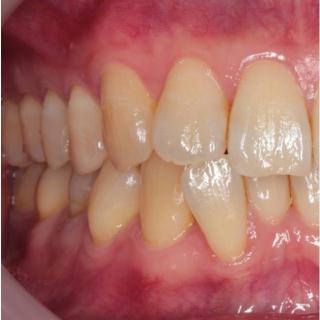

歯並びは正常な位置に生え揃うことが理想的ですが、さまざまな原因で下のように歯並びが乱れてしまう場合もあります。

矯正歯科の目的は、歯並びをゆっくりと美しく治し、心身が健康になることです。

矯正治療は長期にわたるために、治療に関するどんなことでも気軽に話し合いながら、丁寧にコミュニケーションをとりながら、正しい歯並びへと治療を進めてまいります。

矯正装置は種類も数多くありますが、当院では患者様の現在の状態やコスト面などにも考慮して、最適な治療計画を提示しながら治療を提供しています。